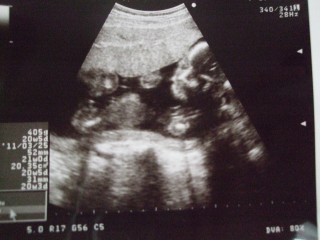

また顔を隠してました。 351gに成長していました。 娘と1gしか違わなくてびっくり。 またお股見せてくれて、やっぱりついてなかったので女の子確定かな? 私が3姉妹なので、念願の姉妹です。 子宮頚管の長さは異常なしでした。 次はクラミジア検査と採血です。 マタニティブルー、少しマシになったかもです。